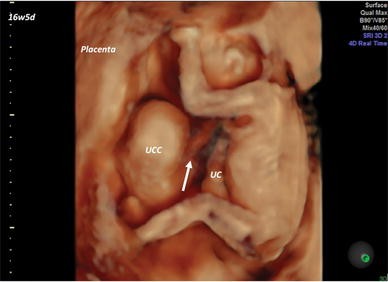

Umbilical Cord Cyst Ultrasound - The colour doppler ultrasound images show anechoic cystic structures with absence of flow, suggesting umbilical cord cysts.

Umbilical Cord Cyst Ultrasound / J clin ultrasound 17:53, skibo lk, lyons ea, levi cs.